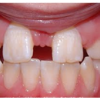

Ülemiste tsentraalsete lõikehammaste (intsisiivide) vahetumine. Retineerunud Intsisiiv

Ülemiste tsentraalsete lõikehammaste (intsisiivide) vahetumine. Retineerunud intsisiivid. Ülemised tsentraalsed esihambad lõikuvad orienteeruvalt 7-8-aastaselt. Enamasti lõikuvad samanimelised jäävhambad paaridena. Normaalne lõikumise järjekord 7, 5-aastselt: vt pilti